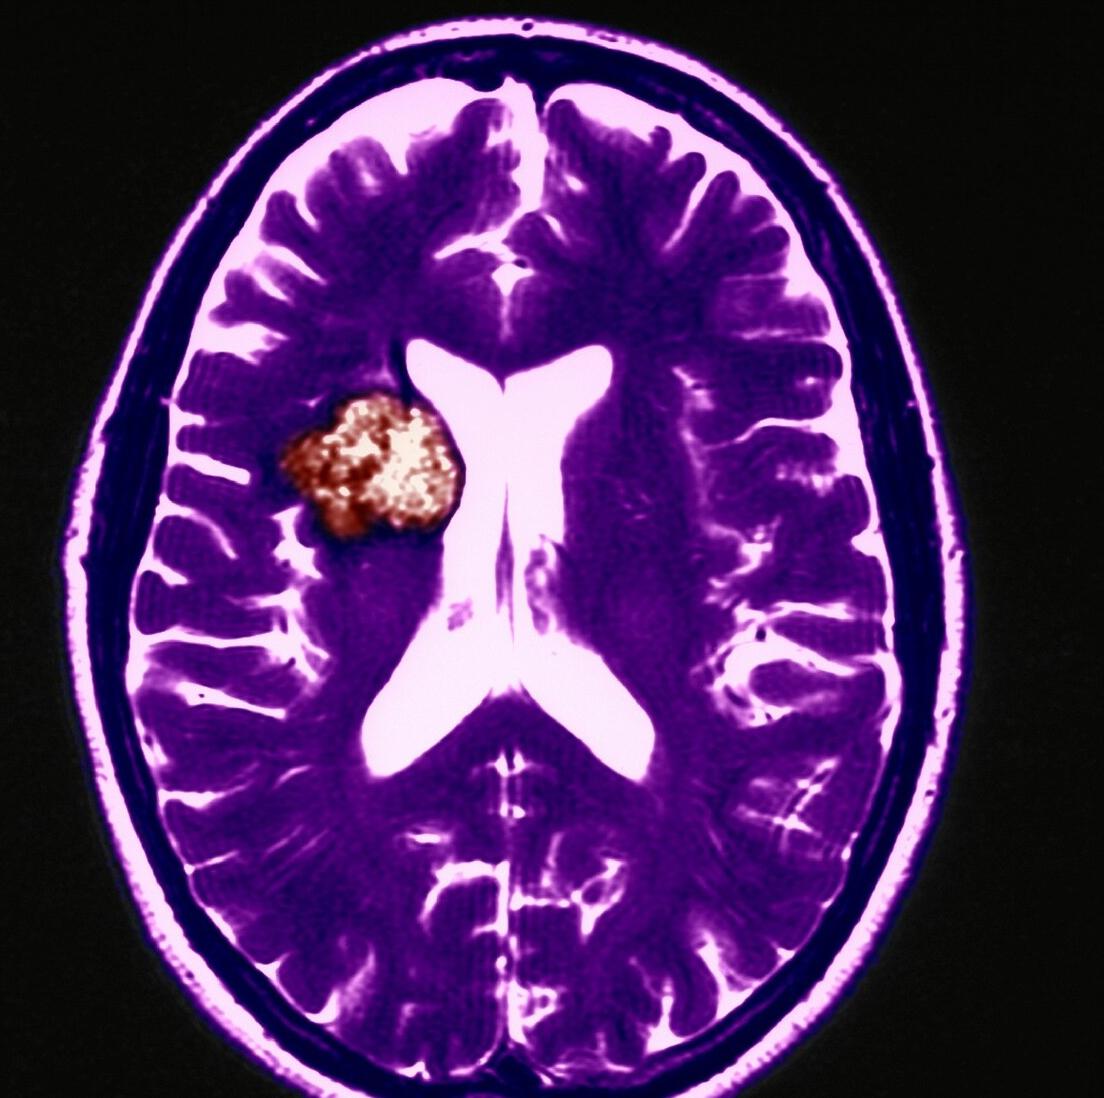

郑州大学附属郑州中心医院接诊了一位男性患者,根据医生介绍,这名男性患者因为大便用劲儿比较大,使他突然间出现了一个头痛的症状,经检查,发现这名患者左侧大脑有个血管瘤破裂出血。

脑血管瘤是脑动脉瘤的俗称,虽然它也是以“瘤”结尾, 但是脑动脉瘤并不属于肿瘤疾病。 它被称为“瘤”是因为动脉血管壁上发生了异常的血管壁膨出,看起来就像是动脉上长出来个瘤子,所以被称为“动脉瘤”。

虽然脑动脉瘤并不是脑瘤,但并不意味着它就很安全!脑动脉瘤被称为脑袋中的“定时*弹炸**”,它最主要的危害就是破裂出血。

一旦发生破裂,大概30%-40%的患者会当场死亡, 即使能够及时抢救并且动了手术,仍然会有不少人会严重残疾。所以,建议大家不要轻视这个疾病!